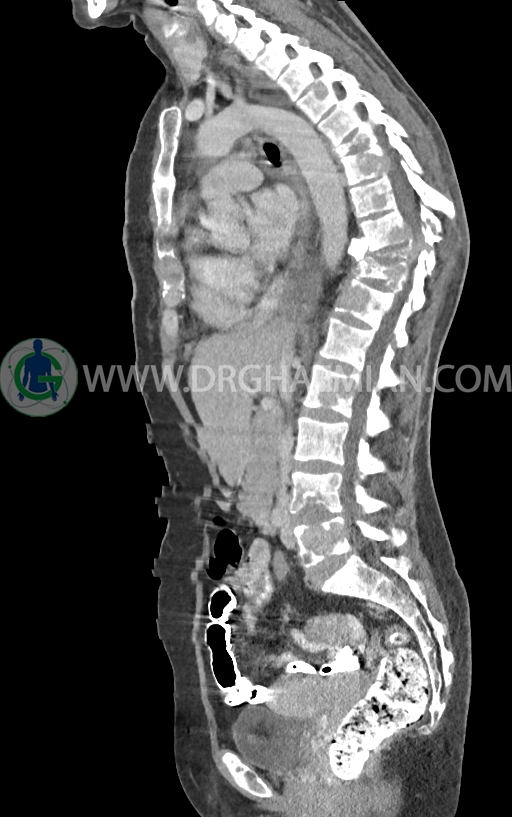

–پلورال افیوژن وسیع دو طرفه

–افزایش ضخامت نسج نرمی و ندولاریته در پلور مدیال ریه چپ یا شاید مربوط به قسمت پره واسکولار مدیاستن با حداکثر ضخامت 10mm در level سوپراهیلار چپ دیده می شود که می تواند مشکوک برای لنفادنوپاتی یا متاستاز باشد.

–لنفادنوپاتی در هیلوم چپ وفضاهای مدیاستن دیده می شود بزرگترین آن ها با SAD=11mm در پره تراکئال دیستال و SAD=14mm در هیلوم چپ و 11mm در ساب کارینا دیده شدند